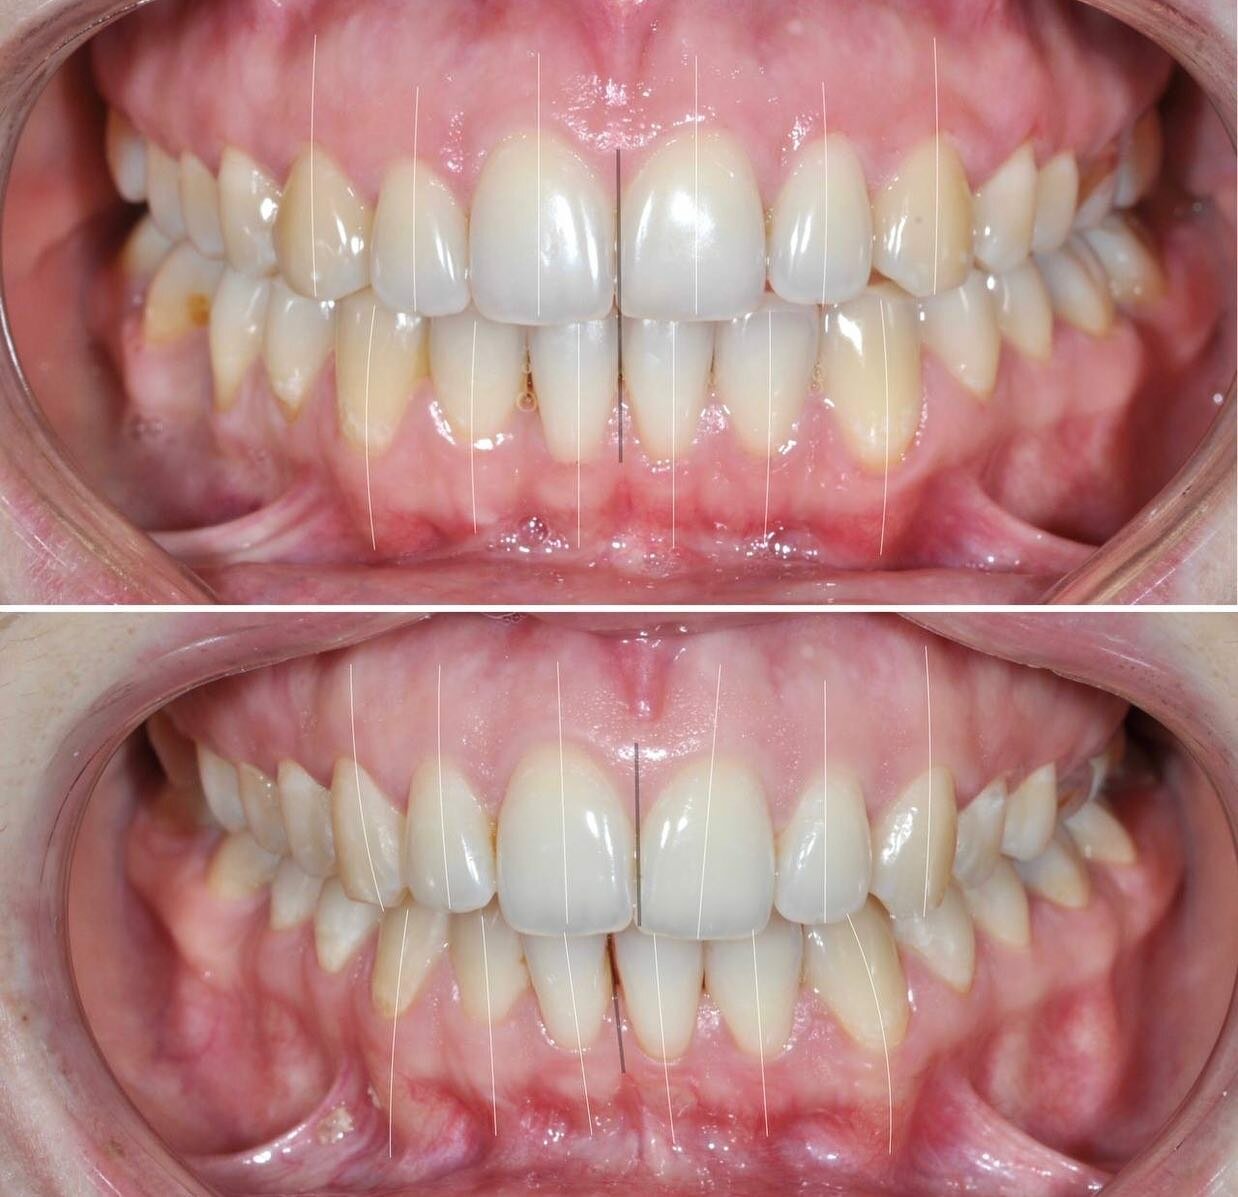

Клиника предоставляет услуги по всем основным направлениям стоматологии, включая общую стоматологию, ортодонтию, хирургическую и эстетическую стоматологию, а также детскую стоматологию. Среди дополнительных услуг: лечение кариеса, пломбирование, удаление зубов, имплантация, протезирование, отбеливание, установка виниров и брекетов, лечение десен и каналов, рентгенография, челюстно-лицевая хирургия и френулопластика.

- ортодонтия

- брекеты

- Положительные впечатления от консультации и установки брекетов.

Записывался на консультацию и дальнейшую установку брекетов для исправления прикуса. Впечатления на данный момент только положительные. Работа аккуратная, отношение вежливое, дополнительных услуг не навязывали.